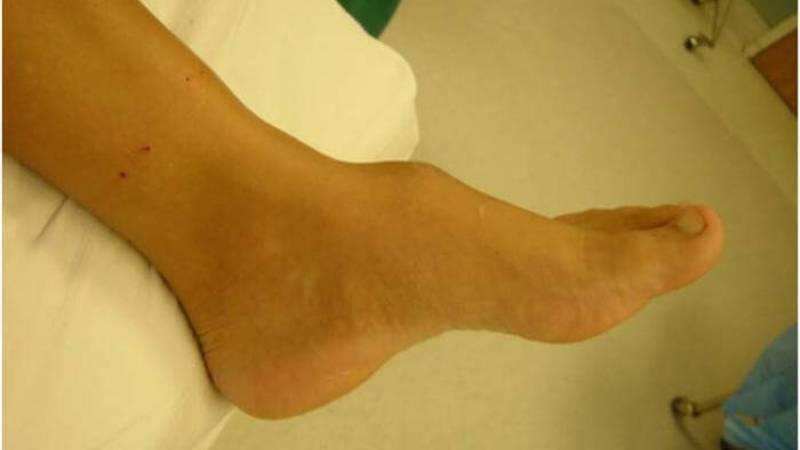

Суть этого нароста заключается в том, что он сначала формируется из хрящевой ткани, а затем постепенно уплотняется и превращается в кость. Существуют также термины, такие как краевые экзостозы, однако чаще всего врачи используют выражение костно-хрящевой нарост (см. фото ниже).

Наиболее часто наросты образуются на концах трубчатых костей, вблизи суставов. Их рост направлен в противоположную сторону. Наиболее распространенным является экзостоз большой берцовой кости, также часто встречаются поражения бедренной кости.

Проблемы могут возникать и с пальцевыми фалангами. Наросты формируются под ногтями и могут достигать размера около 1 см. Это заболевание часто вызывает болевые ощущения, особенно когда ноготь отслаивается и повреждается.